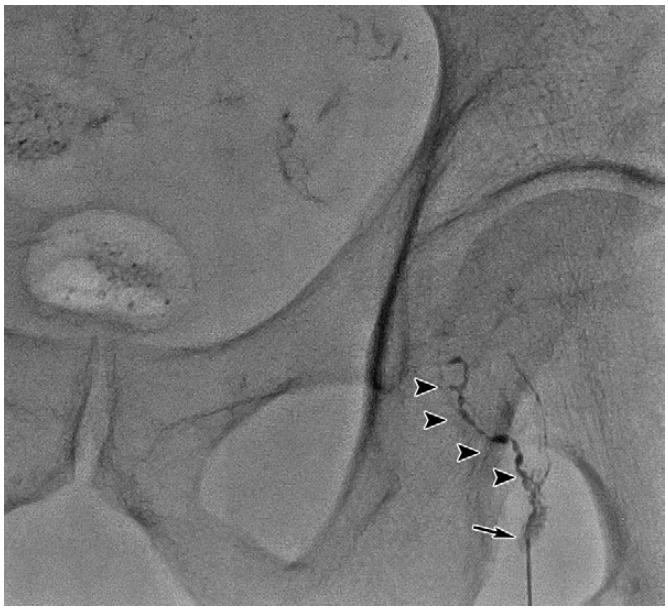

复发/难治性盆腔淋巴囊肿可尝试应用淋巴管栓塞术。在超声引导下,应用微穿针穿刺,微穿针远端置于淋巴结皮质与髓质之间,经微穿针缓慢注入超液化碘油,DSA密切监测淋巴管显影情况,必要时术中CBCT监测淋巴管显影。

超声引导下穿刺淋巴结

DSA下淋巴管造影

当实时显影出现与淋巴囊肿相连接的淋巴管时即可进行栓塞治疗。淋巴管栓塞治疗术后仍需密切观察淋巴囊肿引流量。